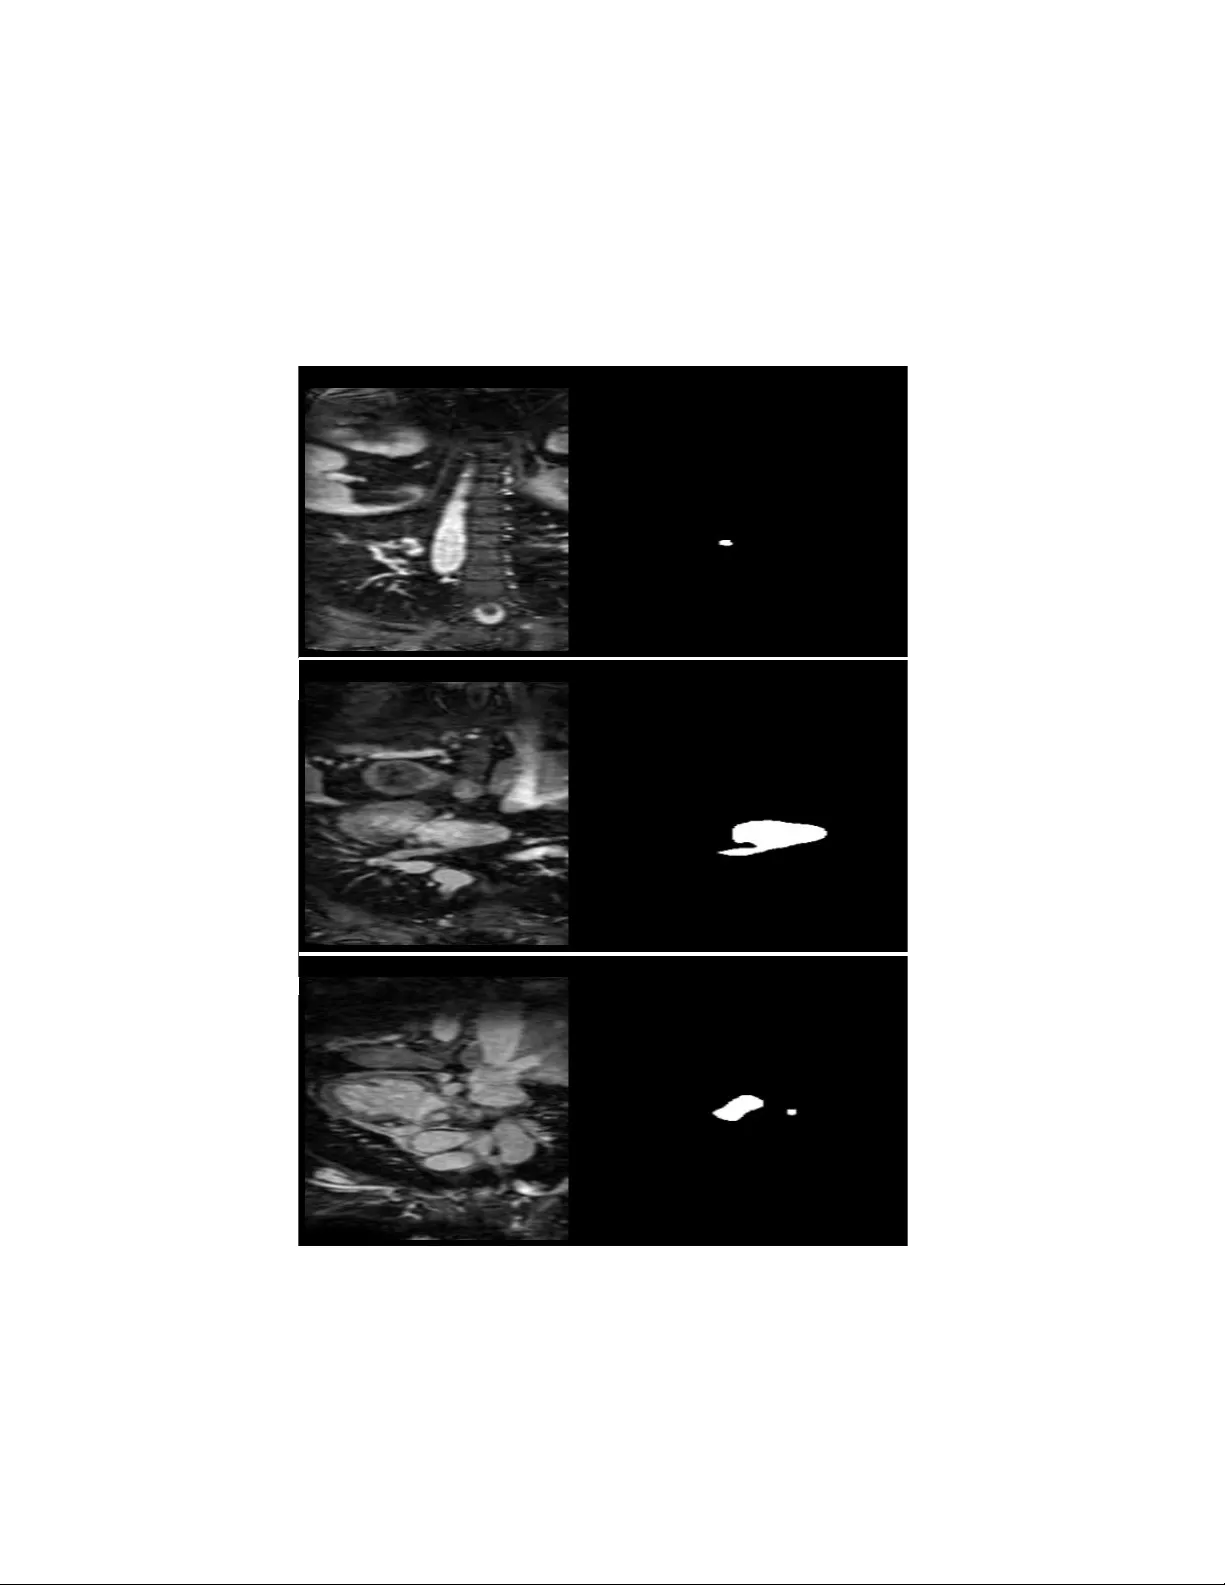

본 연구는 nnU‑Net 프레임워크를 이용해 Left Atrial Segmentation Challenge 2013 MRI 데이터셋(30건)에서 좌심방을 자동으로 분할하였다. nnU‑Net은 데이터 특성에 맞춰 전처리, 네트워크 구조, 학습 파라미터를 자동으로 최적화한다. 5‑fold 교차 검증 결과 평균 Dice 유사도 93.5%를 달성했으며, 기존 전통적 방법들을 능가하였다. 모델은 좌심방 본체와 근위 폐정맥까지 일관된 경계를 재현했으며, 형태·대조·영상 품질 변동에 대해 견고한 일반화 능력을 보였다.

데이터셋은 30개의 고해상도 심장 MRI와 전문가가 만든 라벨 마스크로 구성돼 있다. nnU‑Net은 각 스캔을 0‑1 정규화하고, 동일한 물리적 해상도로 리샘플링한 뒤, 5‑fold 교차 검증을 수행한다. 네트워크는 기본적으로 4개의 다운샘플링 단계와 대응하는 업샘플링 단계로 이루어지며, 각 레벨에서 2개의 3×3×3 컨볼루션 블록과 인스턴스 정규화, LeakyReLU 활성화를 적용한다. 손실 함수는 Dice loss와 Cross‑Entropy loss를 가중 평균한 복합 손실을 사용해 클래스 불균형을 완화한다.

평가 지표는 Dice similarity coefficient(DSC)와 Hausdorff Distance(HD)를 사용했으며, 평균 DSC 93.5%는 기존 논문에서 보고된 85~90% 수준을 크게 초과한다. 특히, 폐정맥 부위에서의 경계 정확도가 향상돼 임상적인 전기생리학 모델링에 직접 활용 가능함을 시사한다. 오류 분석 결과는 주로 심방 근처의 강도 저하 영역과 급격한 형태 변형이 있는 경우에 국한되었으며, 이는 향후 멀티‑모달 입력(예: CT와 MRI 결합)이나 포스트‑프로세싱(조건부 랜덤 필드)으로 보완할 여지를 제공한다.